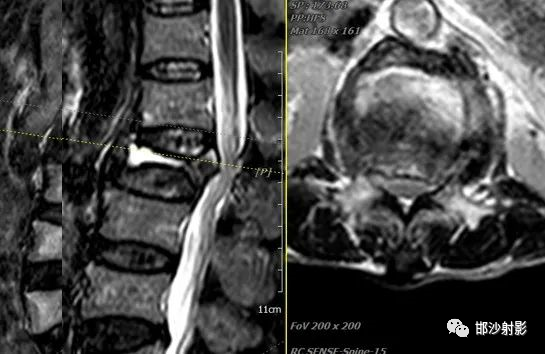

MRI:可以有效评估。根据研究发现,MRI 及病理可将 IVC 表现分四型:①液体型,T1WI 低信号、T2WI 散在高信号, 病理学上为广泛的椎体坏死及坏 死后骨吸收;②压缩型,椎体明显楔形变(前柱明显变扁而后 柱无明显变化),T1WI 低信号,T2WI 中等信号,病理上为椎体 坏死、骨髓纤维化、肉芽及反应性新生骨形成;③肉芽组织 型,T1WI 低信号、T2WI 中等信号, 信号分布较压缩型更广且 椎体后部受累及, 病理学为广泛肉芽组织形成;④混合型, MRI 及病理学为前述各型的混合表现。

真空裂隙征(IVC):是椎体缺血坏死的典型表现,前部较后部多见;IVC为渗液时,T1低信号,T2高信号,此征象称为液体征象,高度提示椎体缺血坏死,并可用于鉴别kummell与骨质疏松引起的压缩性骨折,IVC为气体时,MRI均为低信号。

T2WI,双线征(线样高信号被低信号包绕)

目前关于 Kummell 病影像学表现尚存在争议,暂无统一的影像学诊断标准,IVC、开口现象、双线征为其重要的影像学表现,但均缺乏特异性。而放射性核素骨扫描、SPECT对病变性质不明确或考虑恶性情况时,具有较高的应用价值,在今后的研究中若能将放射性核素骨扫描、SPECT与常规影像学检查结合起来,或许对确立Kummell 病影像学诊断标准有很大的推动作用。